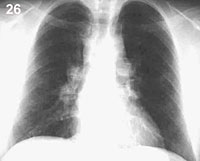

Esquema 26 Comentario placa 26 En el hilio derecho se observa dos masas redondeadas y en el hilio izquierdo es clara la existencia de otra en la parte superior con otra dudosa más abajo. Lo más probable es que se trate de adenopatías hiliares bilaterales, pero es necesaria la placa lateral para establecer su situación con precisión. Examine la placa lateral 27 y ubique las masas. |